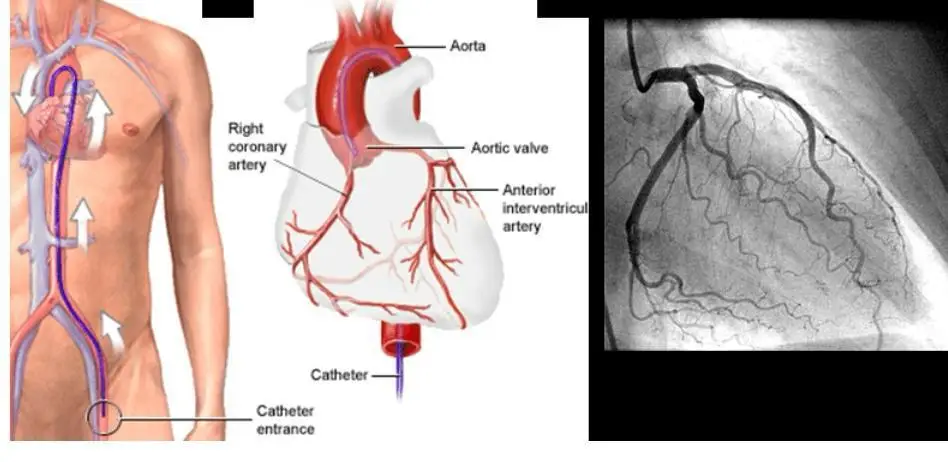

02. Interventional Cardiology

Angiography, Angioplasty with Stent, Pacemaker Implantation, and Device Closures.